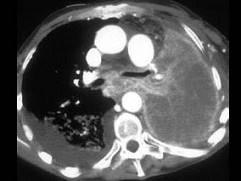

问题 男,68岁,咳嗽,咯血2月余,有40余年吸烟史,请结合影像学检查,选出最可能的诊断 ( )

选项 A、肺脓肿 B、纵隔畸胎瘤 C、肺癌 D、肺结核 E、肺囊肿

答案 C